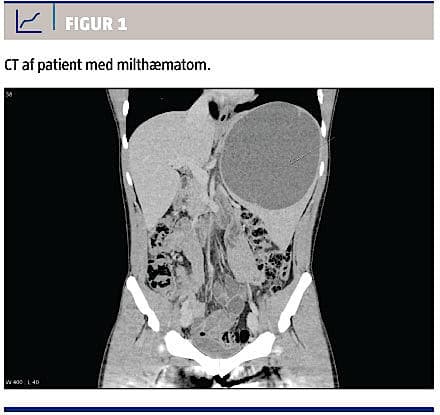

Miltlæsion skal haves in mente ved alle tilfælde af stumpe traumer mod abdomen, særligt i venstre side. Klinisk undersøgelse af abdomen er af lav diagnostisk værdi i forhold til at udelukke intraabdominal skade, hvorimod positive fund i form af peritoneal reaktion eller distenderet abdomen giver kraftig mistanke om en behandlingskrævende lidelse. Af denne årsag er billeddiagnostik en nødvendighed ved mistanke om miltlæsion. Focused assessment with sonography for trauma (FAST) er en hurtig ultralydundersøgelse, hvormed man med en sensitivitet og en specificitet på knap 100% (hos voksne) kan påvise fri væske intraperitonealt som tegn på blødning fra milten eller andre organer [5]. Uanset fundene ved FAST foretages der CT med i.v. kontrast givet i tidlig arteriel og venøs fase hos en stabil patient, hvor man har mistanke om miltlæsion,. Herved visualiseres milten og eventuelle læsioner, herunder milthæmatomer (Figur 1). Graden af miltskaden kan herefter fastslås ved brug af American Association for the Surgery of Trauma (AAST) Injury Score [6] (Tabel 1). Ved stumpe abdominale traumer har CT en sensitivitet på over 90% og en specificitet på næsten 100% – og højere værdier ved milt- og leverskade end ved tarmlæsion [7].